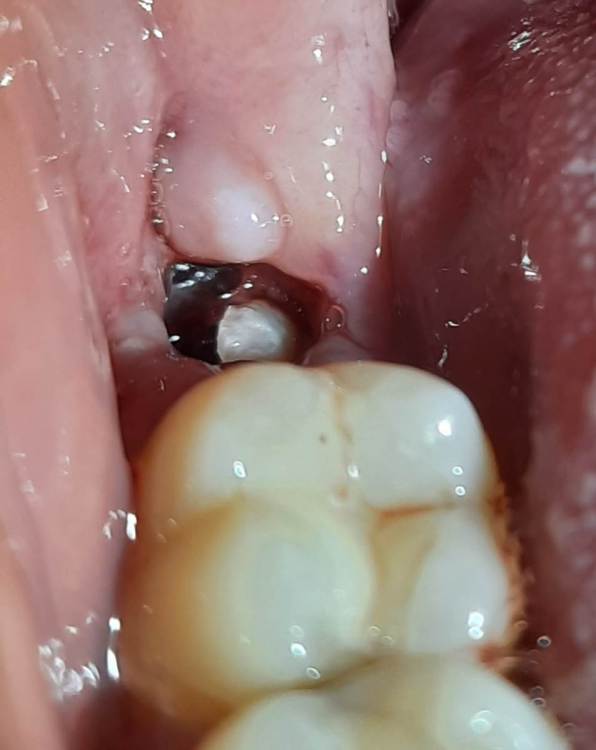

SebaPaseba Опубликовано 13 ноября, 2022 Поделиться Опубликовано 13 ноября, 2022 (изменено) Здравствуйте! Очень нужна ваша помощь/мнение/консультация/совет. Девушка, 22 года. 10.11.2022 в 12:00 мне удалили нижнюю восьмёрку справа (над ней был капюшон из десны и за несколько дней до удаления там произошло воспаление, которое сопровождалось небольшим отёком щеки, сильными болями при глотании, увеличенными лимфоузлами с той же стороны, болью в челюсти и под челюстью). Перед удалением, 08.11.2022 была проведена профессиональная чистка зубов. После удаления врач положил в лунку какую-то мазь и отпустил с миром. Кровь долго не останавливалась, зато боли прекратились очень быстро. Вечером в день удаления челюсть и десны ещё болели от уколов анестезии и от недавнего воспаления, а на следующий день уже всё сошло на нет и болей нет до сих пор. Так же после удаления не было отёка и в целом самочувствие хорошее. Но лунка всё ещё немного кровит (в основном ближе к ночи). В день удаления ничего не предпринимала, поела только спустя часов 8-9, зубы перед сном не чистила. На следующий день после удаления стала делать ванночки с хлоргексидином и осторожно чистить зубы. Поднималась ненадолго температура до 37/5. Вчера в лунку попал кусочек еды. Я пыталась его вымыть водой (не полоская, а просто наклоняя голову то в одну то в другую сторону), но это не помогло и кусочек лишь сдвинулся из центра к краю лунки. Оставлять его там я побоялась, чтоб не спровоцировать инфекцию, и максимально осторожно достала зубочисткой, почти не прилагая усилий, чтоб не повредить сгусток. Сразу после этого всё было хорошо, но спустя некоторое время (полчаса-час) лунка снова начала кровить. Сегодня там чётко видно какое-то белое образование, похожее на кусочек еды. Эта штука была там и вчера (ещё до попадания еды в лунку), и она с каждым днём как будто становится больше. Я не понимаю, это нормальный процесс заживления или нужно начинать беспокоиться? Очень боюсь, что это альвеолит. Прямо сейчас, кажется, присутствует не очень приятный запах изо рта (но не сказать, что прям гнилостный). Лимфоузлы под челюстью всё ещё слегка увеличены, но не болят. Лунка вновь кровит немного. Боли полностью отсутствуют, иногда бывает ощущение пульсации. Температура 37/3 (не знаю, от воспаления или нервов, просто я ОЧЕНЬ СИЛЬНО нервничаю последние дни). К врачу смогу попасть в лучшем случае только завтра, а паниковать начинаю уже сейчас. Пожалуйста, посмотрите и скажите, может ли это быть отклонением? 1 фото - состояние вечером 11.11.2022 2 фото - состояние вечером 12.11.2022 3 фото - состояние сейчас 13.11.2022 Изменено 13 ноября, 2022 пользователем SebaPaseba Ссылка на комментарий

Irouil Опубликовано 13 ноября, 2022 Поделиться Опубликовано 13 ноября, 2022 Альвеолит - болит, появляется начиная где-то с 5-го дня. Пока все выглядит нормально Уже можете начинать аккуратно полоскать, лёгкое подкравливание десны на этом этапе не опасно 1 Ссылка на комментарий

SebaPaseba Опубликовано 13 ноября, 2022 Автор Поделиться Опубликовано 13 ноября, 2022 @Irouil спасибо за ваше мнение. Немного успокоили. Особенно по поводу кровоточивости. Боли иногда бывают, но они очень редкие и слабые. Списываю это скорее на естественные последствия после удаления. А насчёт белого образования - это может быть фибрин? И нормально ли, что он выглядит как шарик? Просто видела на сайтах информацию, что он вроде как образуется по всей поверхности лунки в виде налёта Ссылка на комментарий